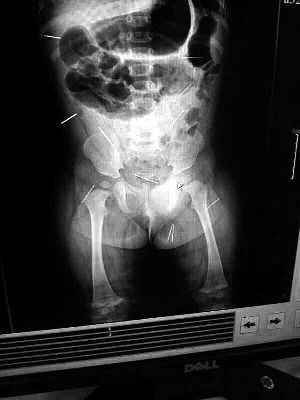

山東聊城11個(gè)月女嬰萱萱(化名)疑似被人以12根鋼針插滿臀部、腹腔等部位,昨天在兒童醫(yī)院會(huì)診后,醫(yī)生稱3根針靠近胸腔最危險(xiǎn),首批先行取出,預(yù)計(jì)將在下周二手術(shù)。孩子父母稱孩子一直由家人照顧,自家與他人并無(wú)冤怨。山東警方表示正在偵破中,不便透露案情。

“要不是當(dāng)初那幾個(gè)紅點(diǎn),可能到現(xiàn)在我們還不知道孩子身體里有鋼針!”昨天,在兒童醫(yī)院住院處,萱萱爸爸范先生稱,日前原本很愛笑的萱萱突然變得有些焦躁,一抱起來(lái)就哭,孩子母親偶然間在萱萱屁股上發(fā)現(xiàn)了幾個(gè)小紅點(diǎn)兒,原以為是蚊蟲叮咬,就醫(yī)結(jié)果卻讓人不寒而栗?!搬t(yī)院拍出的片子上,萱萱的體內(nèi)有12根鋼針,插滿臀部、腹腔、骨盆等各個(gè)部位。”范先生介紹,因?yàn)殇撫樢焉钊塍w內(nèi),要是孩子不哭鬧,他們很難發(fā)現(xiàn)。

北京晨報(bào)記者了解到,目前體內(nèi)的12根鋼針多分布在孩子的臀部,一根在腹部,其余3根在胸腔附近,其中一根很接近心臟。“因?yàn)楹⒆犹?,醫(yī)生們害怕取針的時(shí)候?qū)λ斐蓚?,在胸腔附近?針可能會(huì)威脅她的生命”。